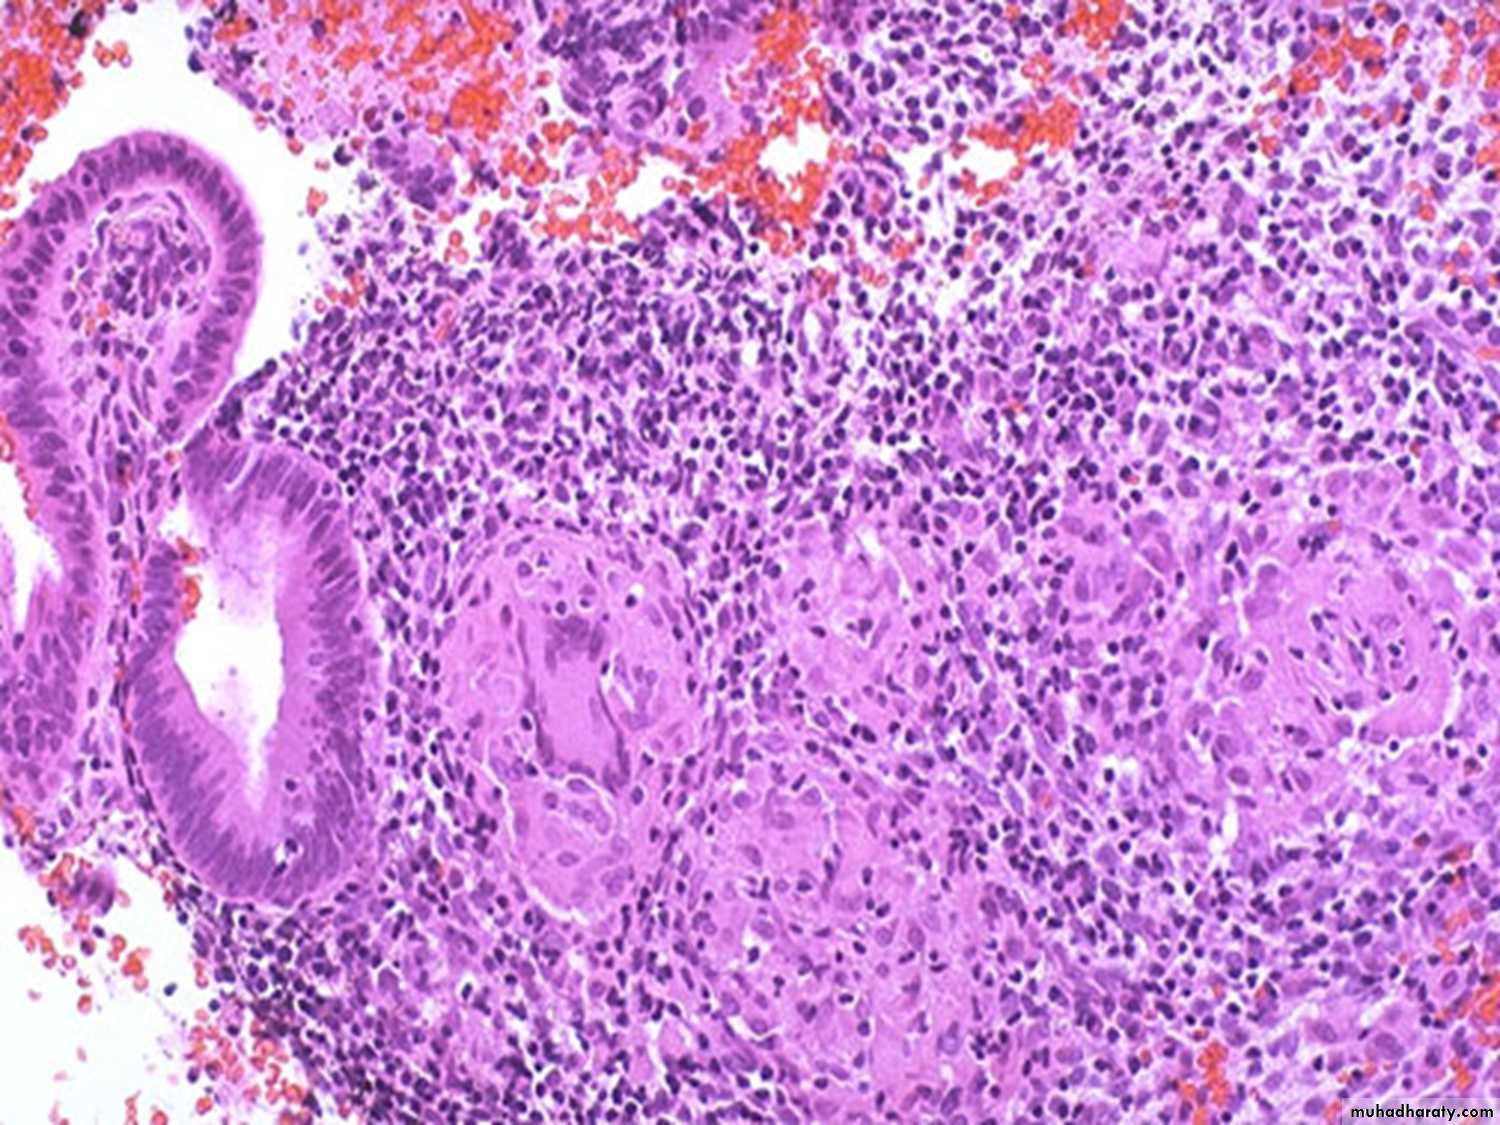

Microscopically :

The tumor is composed of cluster of cytotrophoblast separated by streaming masses of syncytiotrophoblast ,resulting in a characteristic dimorphic plexiform pattern .Villi are characteristically absent as a matter of fact ,their presence is said to rule out the diagnosis of choriocarcinoma .No matter how atypical the trophoblastic cells may be .

The natural history of untreated choriocarcinoma is characterized by the development of early hematogenous metastasis ,the most common sites being the lung, vagina, brain, liver, kidney &bowel & often present with massive hemorrhage .